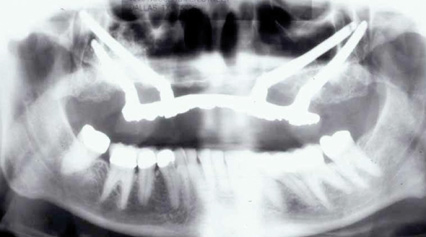

Interceptive implant therapy may then become a consideration earlier in life to create restorations that will not be subject to the latent effect of dental caries as aging continues. An example is shown in Figure 6 and Figure 7; the panoramic film of a 56-year-old man shows several orthognathic and extensive dental procedures historically. All full-coverage restorations had been replaced for a second time, and, again, all evidenced recurrent caries, but the existing dentition was periodontally sound and relatively esthetic.

Fig 6. Panoramic radiograph of 56-year-old patient illustrating a number of dental procedures historically.

Figure 6

Fig 7. Existing dentition was sound periodontally and reasonably esthetic.

Figure 7